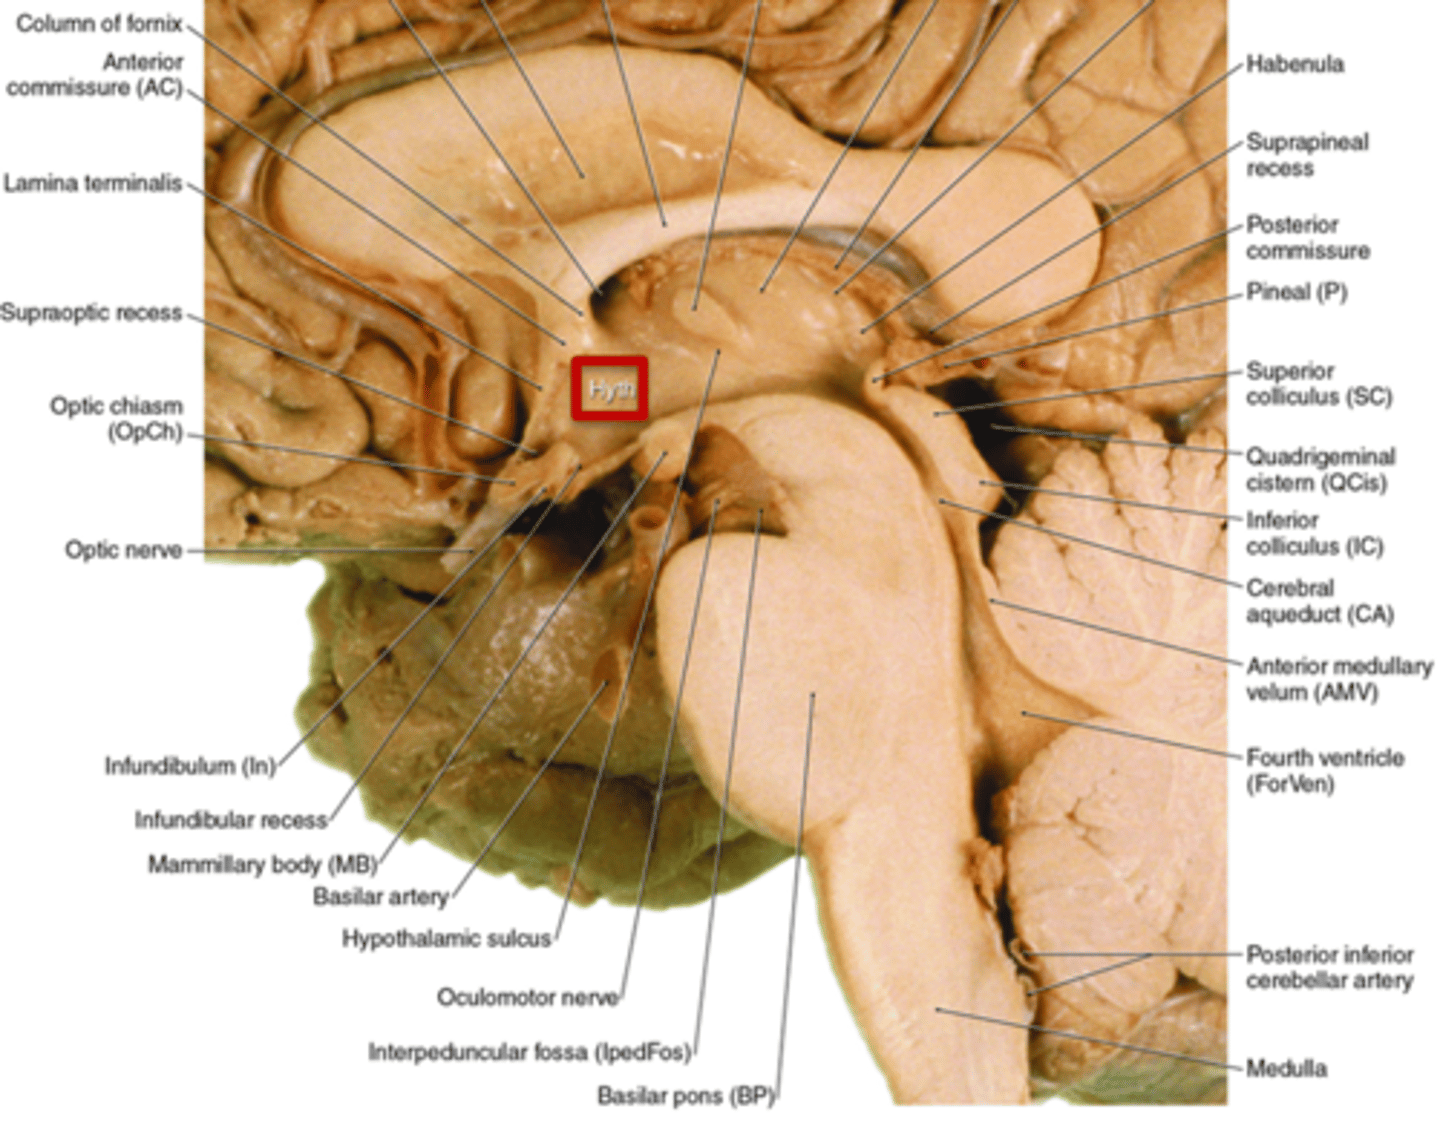

what are 2 important structures of the diencephalon?

1. thalamus

2. hypothalamus

what structure of the diencephalon is the main visceral control center of the brain?

hypothalamus

what structure of the diencephalon mediates a wide range of functions through connections with endocrine, autonomic, somatic motor, limbic systems, and maintaining a state of homeostasis?

hypothalamus

what are the 3 parts of the brainstem?

1. midbrain

2. pons

3. medulla

which region of the brainstem contains the cerebral aqueduct?

midbrain

looks like a hole in the center of the midbrain

cerebral aqueduct connects the 3rd and 4th ventricles